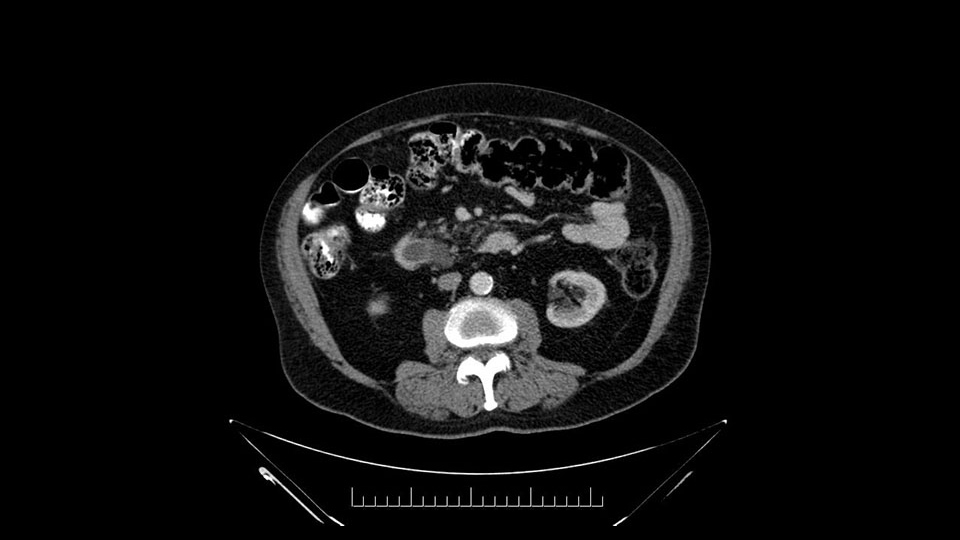

Then look at the first jejunal branch - which is this thing here - this little branch which goes under the SMA. It’s something that we’ve just started appreciating over the past few years and the reason for that is: there’s two or three small branches that come out of the uncinate into the the first jejunal and it’s a fairly inevitable part of the operation where there’s some bleeding. As long as you’re cognizant of what’s happening, it’s no reason to panic and that kind of bleeding will eventually stop or can be stopped but it’s not easy because these little vessels are fragile from the uncinate to the first jejunal. So I do focus on that and it’s pretty consistent I’d say 9 times out of 10, people have that first jejunal.